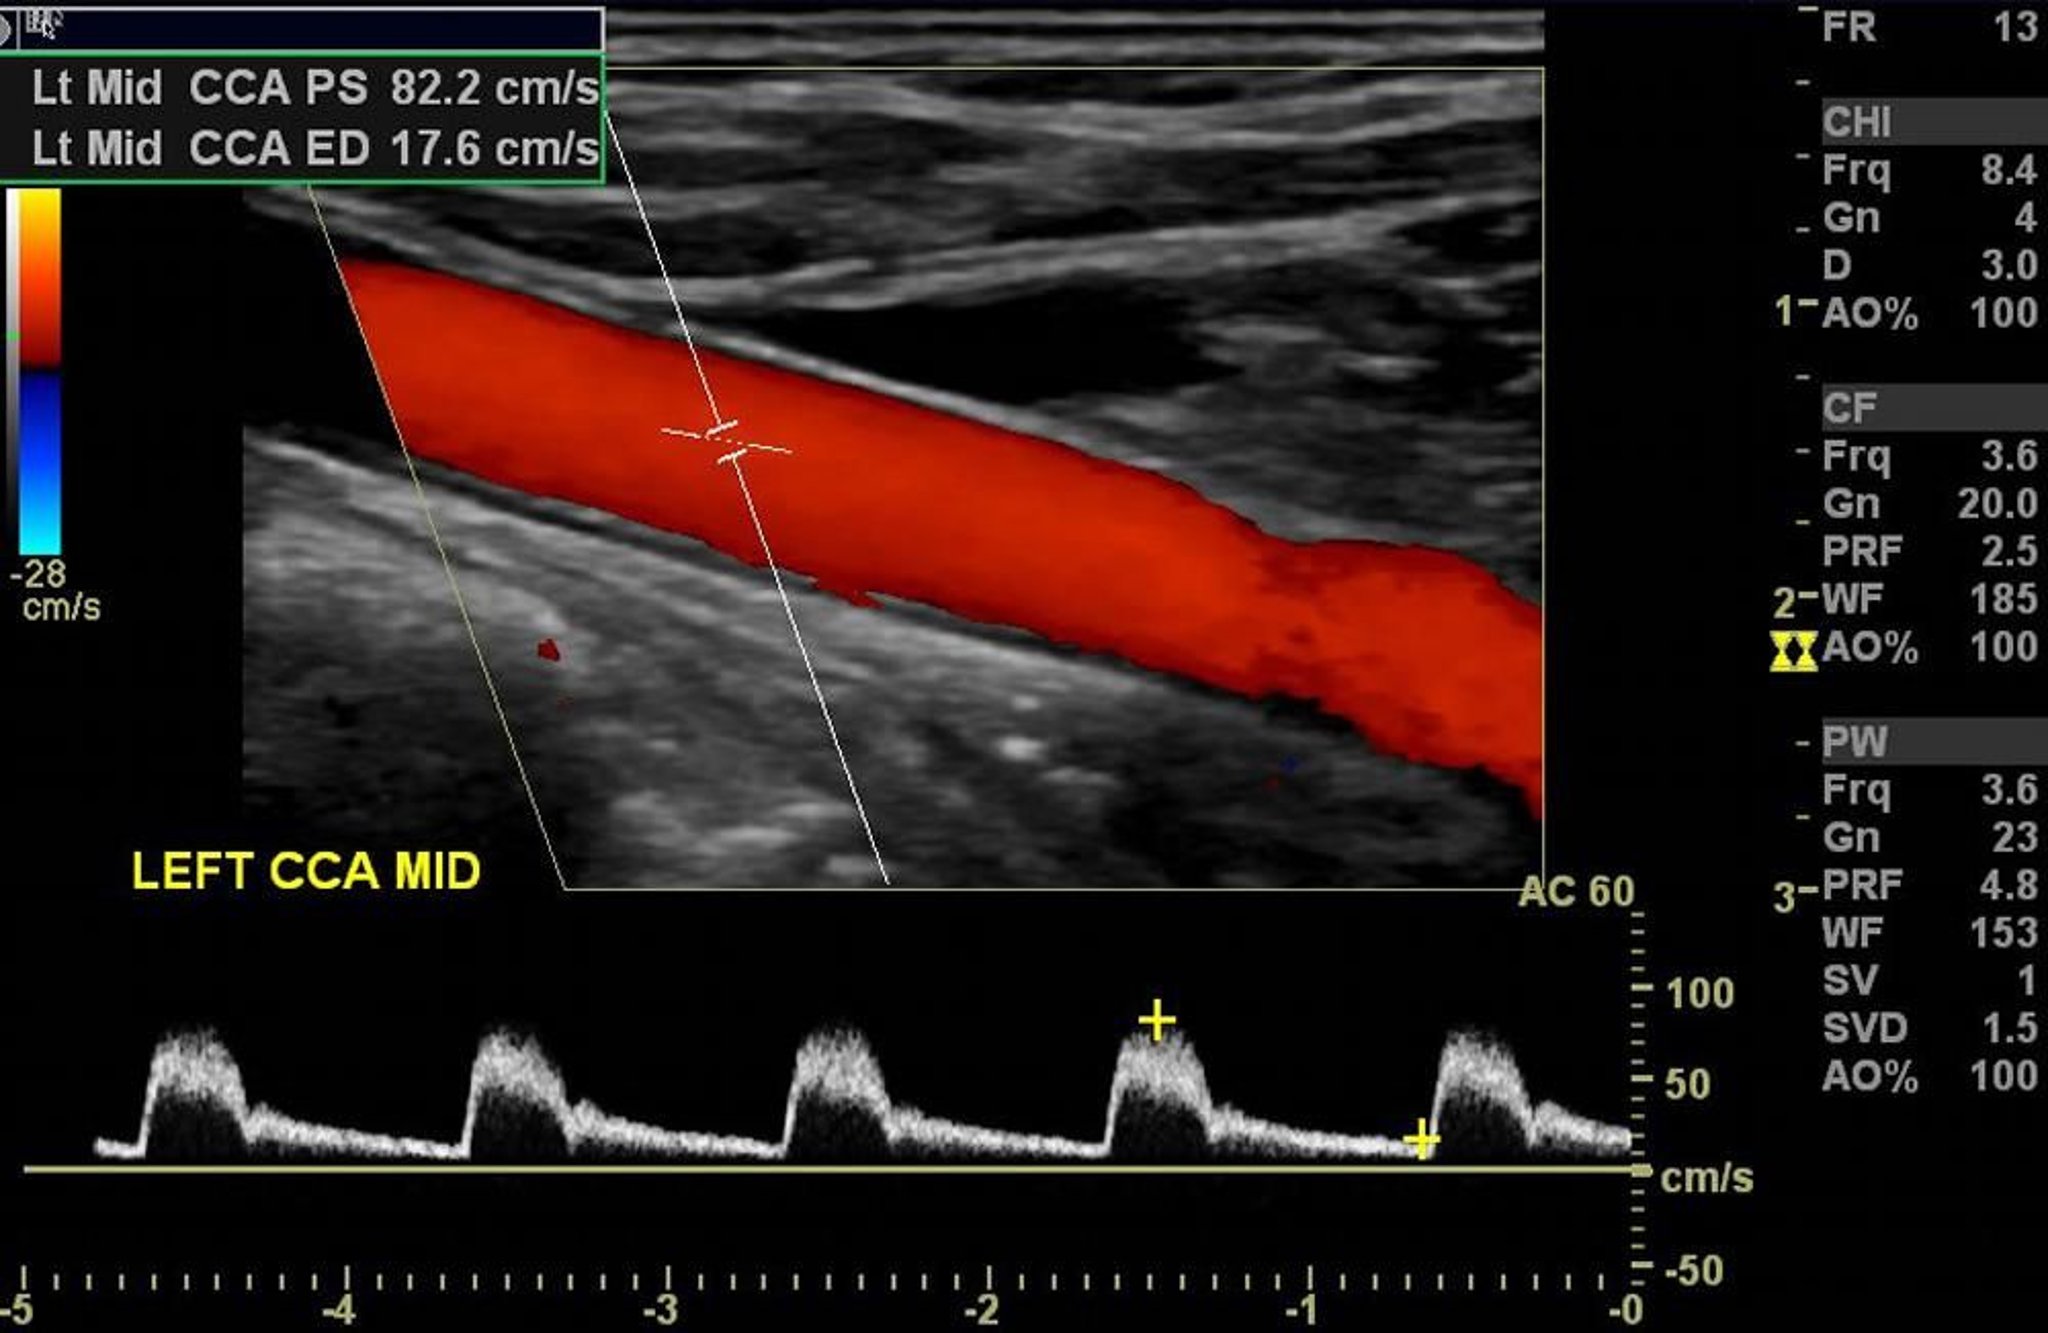

カラードプラ超音波検査

この左頸動脈のカラードプラ超音波検査では,有意な狭窄のない正常な動脈血流がみられる。

Image courtesy of Hakan Ilaslan, MD.